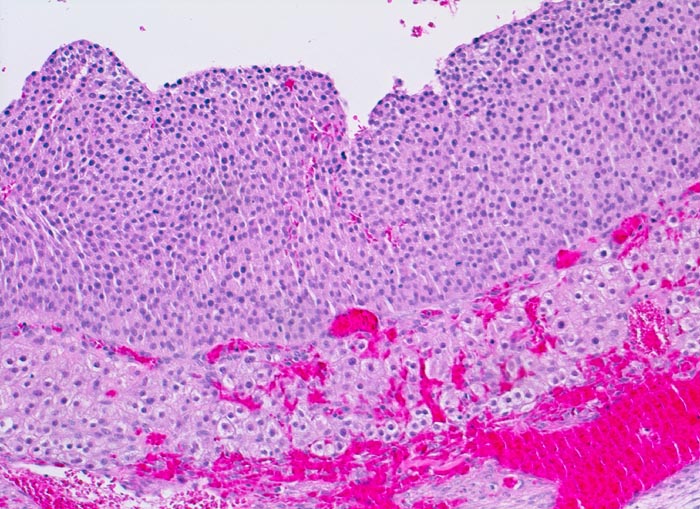

Rupturierter Follikel

Zum Follikellumen hin eine breite Schicht von kleinen Granulosazellen. Gegen aussen folgt die stark vaskularisierte Theca interna mit grösseren luteinisierten Zellen.